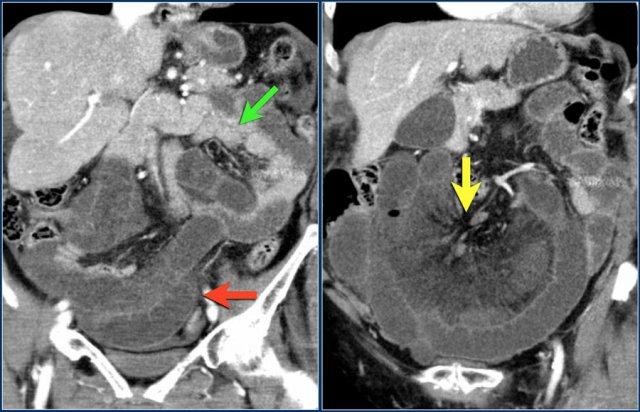

Đây là hình ảnh bệnh nhân thiếu máu cục bộ ruột do huyết khối tĩnh mạch mạc treo tràng trên – SMV (mũi tên đỏ).

Lưu ý tình trạng ứ máu tĩnh mạch trong mạc treo ruột (mũi tên vàng).

Đây là một bệnh nhân khác bị thiếu máu cục bộ một đoạn dài ruột non do tắc ruột quai kín.

Một đặc điểm hình ảnh quan trọng của tắc ruột quai kín là hình ảnh các quai ruột non giãn xếp theo kiểu nan hoa bánh xe với các mạch máu mạc treo hội tụ về một điểm trung tâm.

Các dấu hiệu thiếu máu cục bộ trong tắc ruột quai kín tương tự như ở các bệnh nhân có nguyên nhân thiếu máu cục bộ mạc treo khác:

- Dày thành ruột

- Phù nề mạc treo ruột

- Cổ trướng

- Sự ngấm thuốc của thành ruột trong thiếu máu cục bộ có thể bình thường, tăng do hiện tượng tái tưới máu, hoặc giảm/mất ngấm thuốc như trong trường hợp này.